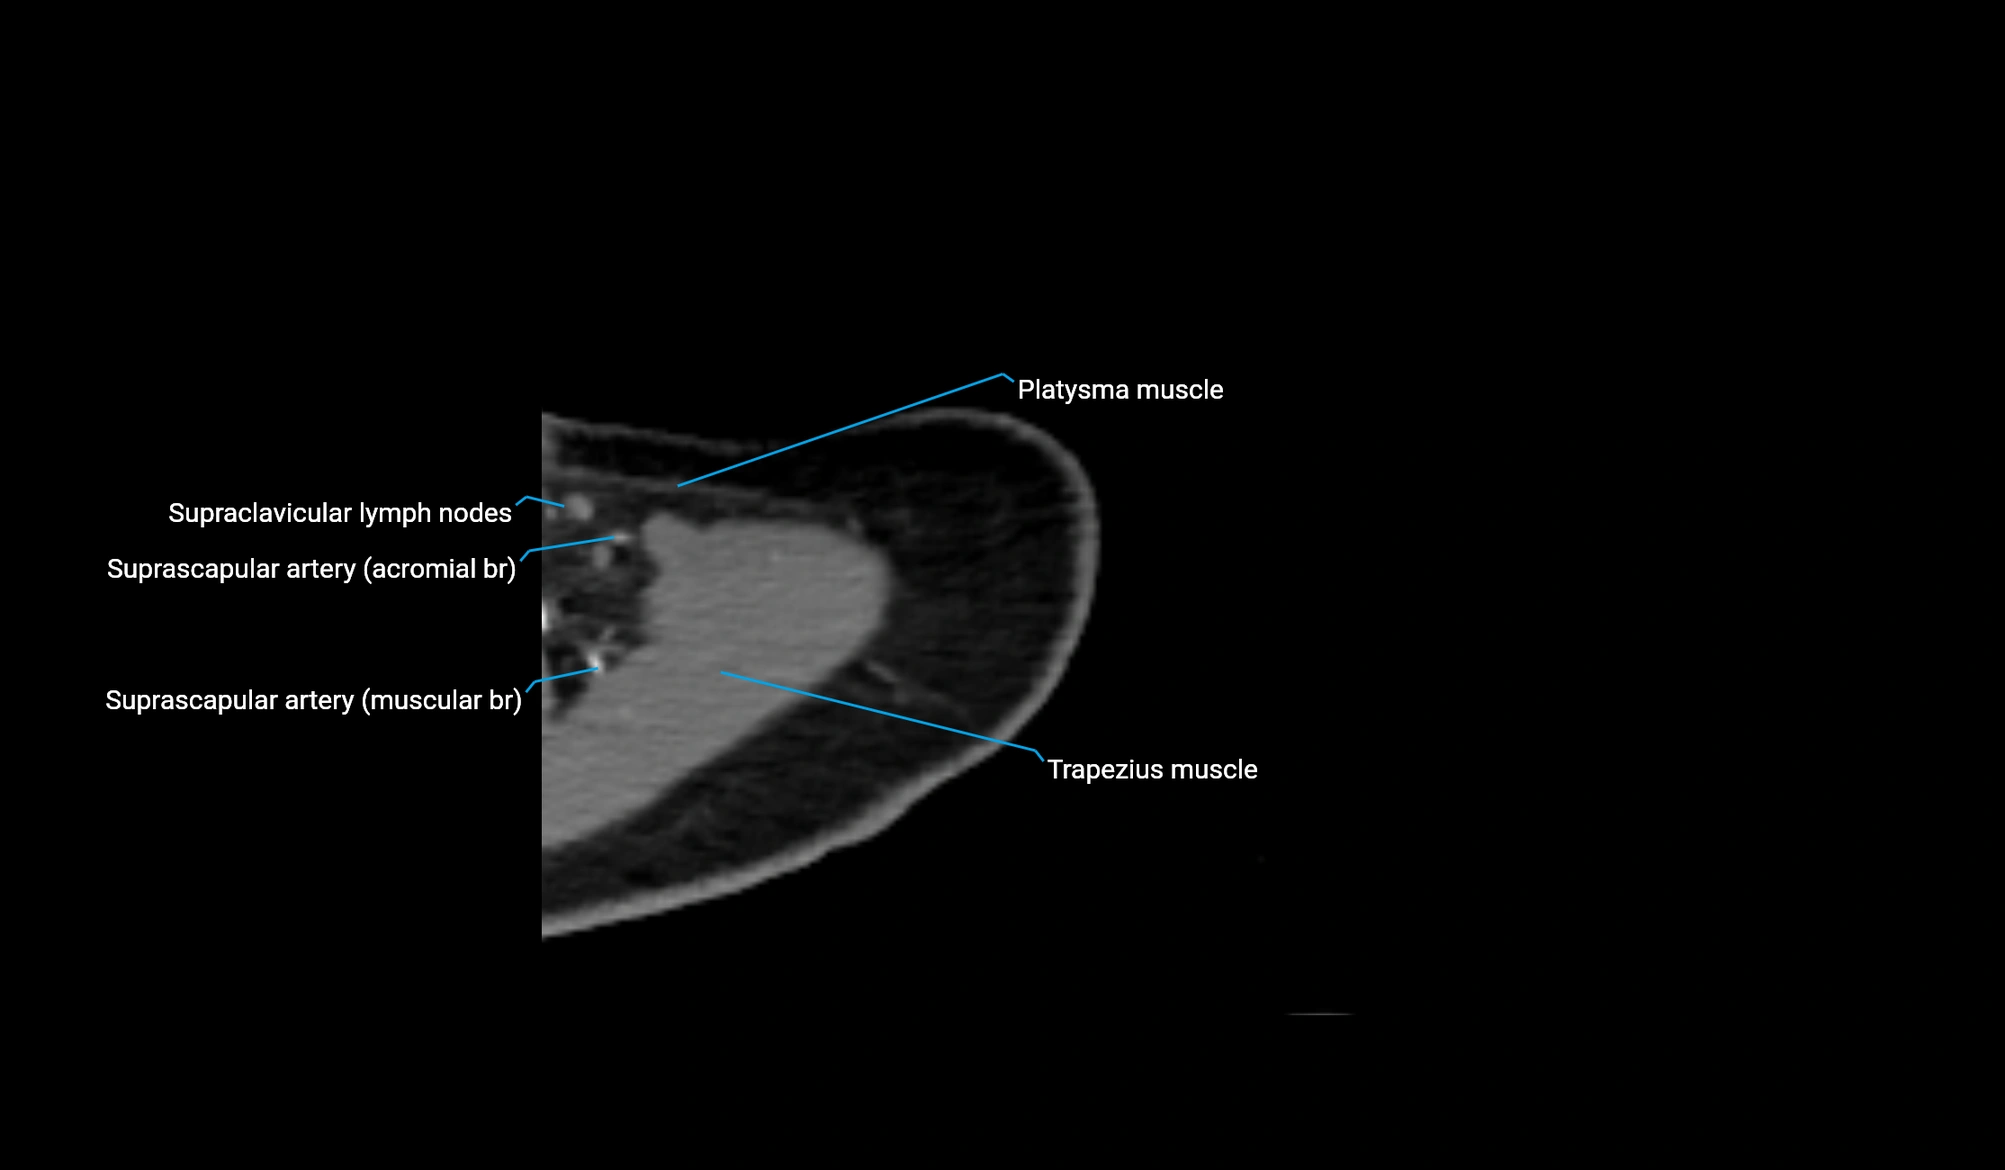

CT image